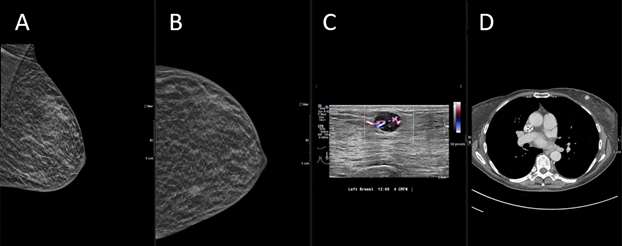

Breast metastasis from possible appendiceal carcinoid tumor:

Case: Metastasis to the Breast From a Non-breast Primary Cancer Figure 3

Figure 3: (A-B) On MLO and CC mammogram images respectively, there are oval masses with circumscribed margins seen in the left breast. (C) Ultrasound demonstrates multiple circumscribed oval masses, the largest measuring 11 x 8 x 12 mm seen in the left breast at 2 o'clock located 7 centimeters from the nipple. (D) Corresponding CT chest with left breast rounded mass.